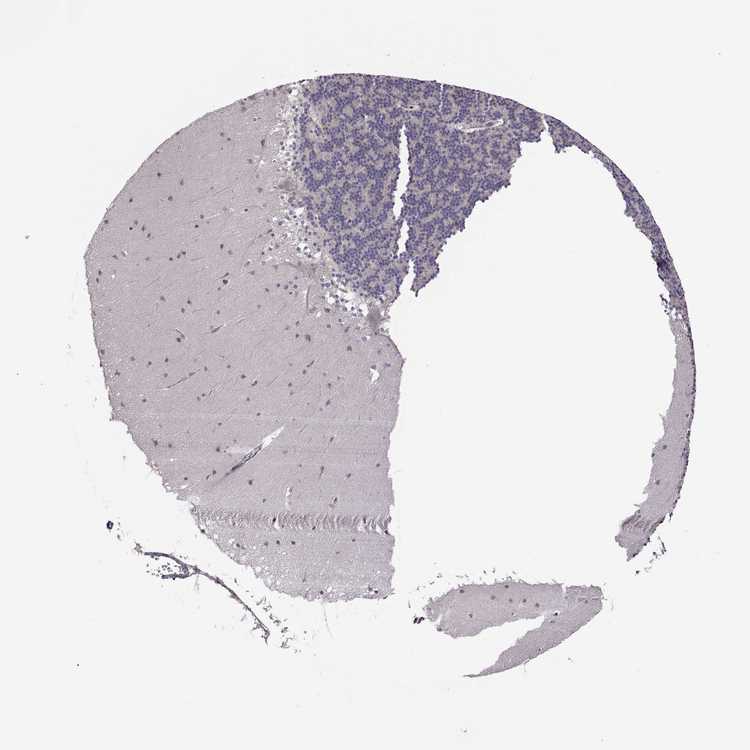

CEREBELLUM - Antibody stainingi

Antibody staining in the annotated cell types in the current human tissue is reported as not detected, low, medium, or high, based on conventional immunohistochemistry profiling in selected tissues. This score is based on the combination of the staining intensity and fraction of stained cells.

Each image is clickable and will lead to virtual microscopy that enables deeper exploration of all samples and also displays staining intensity scores, fraction scores and subcellular localization as well as patient and tissue information for each sample.

Antibody HPA075570

Purkinje cells Not detected

Cells in granular layer Not detected

Cells in molecular layer Medium